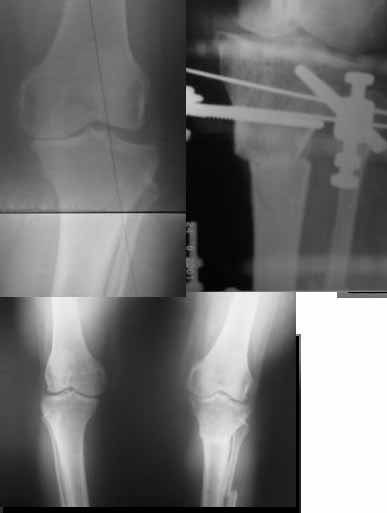

Very nice correction but, to my eye there is some 'over' correction of the tibia, now in some proximal valgus?

What is the hka?

What about the P/F joint orientation.

Alex, with your permission I will run our alignment analaysis program on your long leg views and give you some correction options?

Yesterday i performed correction of one leg (the plan to make both in one session was cancelled because of some external reasons). Suggestions of Nuno Lopes were most close to my view. A small wire distractor was used intraoperatively. Derotation ~6-7 degrees was performed also. CT scans evaluating rotation will be available only

tomorrow. No problem to change rotation of the operated limb in the moment of the second surgery. Comments/critics are welcome.

Can the attached result be analyzed by the software?